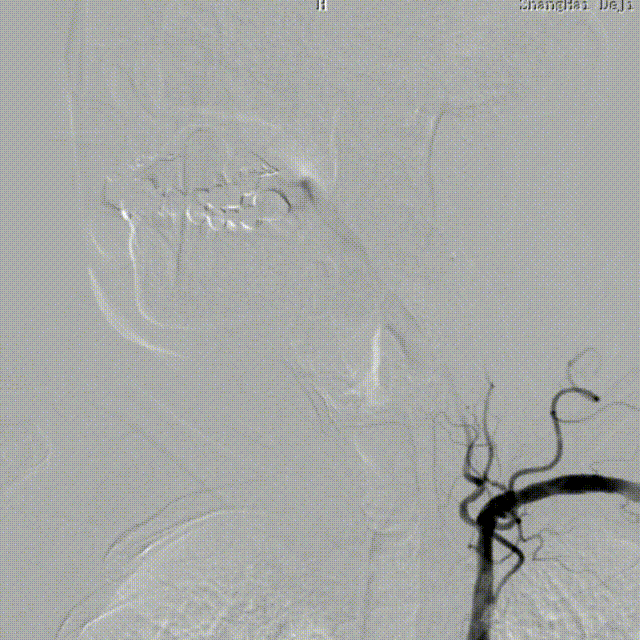

造影见LV闭塞,立即沿0.014*200cm 通桥北斗SS™神经血管导丝置入3mm*16mm 药物球扩支架至LV1。

压力泵逐渐加压球扩支架到8atm, 支架打开良好,造影示残余狭窄0%。

双侧锁骨下动脉造影见椎动脉、基底动脉血流通畅,远端未见栓塞表现。

术后头晕呕吐,当日DWI:左侧小脑梗死,MRA未见明显大血管栓塞。